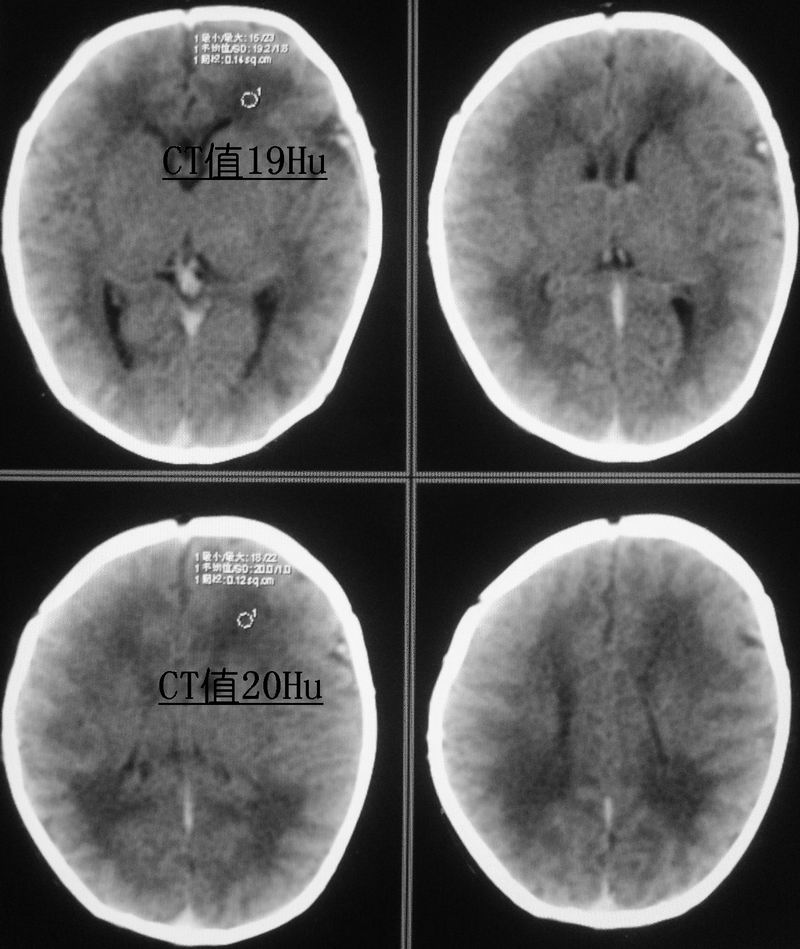

新生儿,男性,5天,出生时有短暂窒息史。现一般情况较好,面色红润,无明显发绀,原始反射尚可。经治医生和家属均不放心,要求ct。

小孩脑实质内可见多发对称性低密度灶,ct值17~20hu,我也考虑有缺血缺氧性脑病存在。

可问题是患儿虽有短暂的窒息史,却并没有明显的临床症状,实在不好解释。这就牵涉到新生儿的脑的正常ct值的问题,为此专门查了一点资料:

曹连义等曾报道足月新生儿脑组织ct值明显低于儿童及成人,建议新生儿期ct正常值为18~40 hu,低于18 hu为低密度[1-2]。对不同胎龄新生儿脑组织ct值正常范围及平均值国内未见报道。本研究显示即使新生儿期若胎龄不同,各部位脑组织(小脑、脑干、基底节、丘脑、白质、灰质)ct值均明显不同,胎龄越小,脑ct值越低,与国外学者报道一致[3]。其原因:(1)与脑组织含水量有关,胎龄越小,脑组织含水量越多;(2)胎龄越小,神经细胞髓鞘形成越不完全。故足月新生儿脑组织ct值正常范围不适用于早产儿,不同胎龄新生儿应有不同的正常值,这样才不致于将早产儿正常发育过程中的脑组织低密度误诊为脑水肿、缺氧缺血性脑病。

新生儿缺血缺氧性脑病的诊断应紧密结合临床.片上所见之对称性稍低密度影,很可能是窗宽窗位未调好,本人在工作中也遇到过这种情况,调节好窗宽窗位可避免误诊.新生儿及儿量脑细胞水份含量多于成人,因此脑实质密度更低,脑沟亦较浅.

新生儿缺血缺氧性脑病的诊断应紧密结合临床;脑白质ct低于18hu考虑缺血缺氧改变。